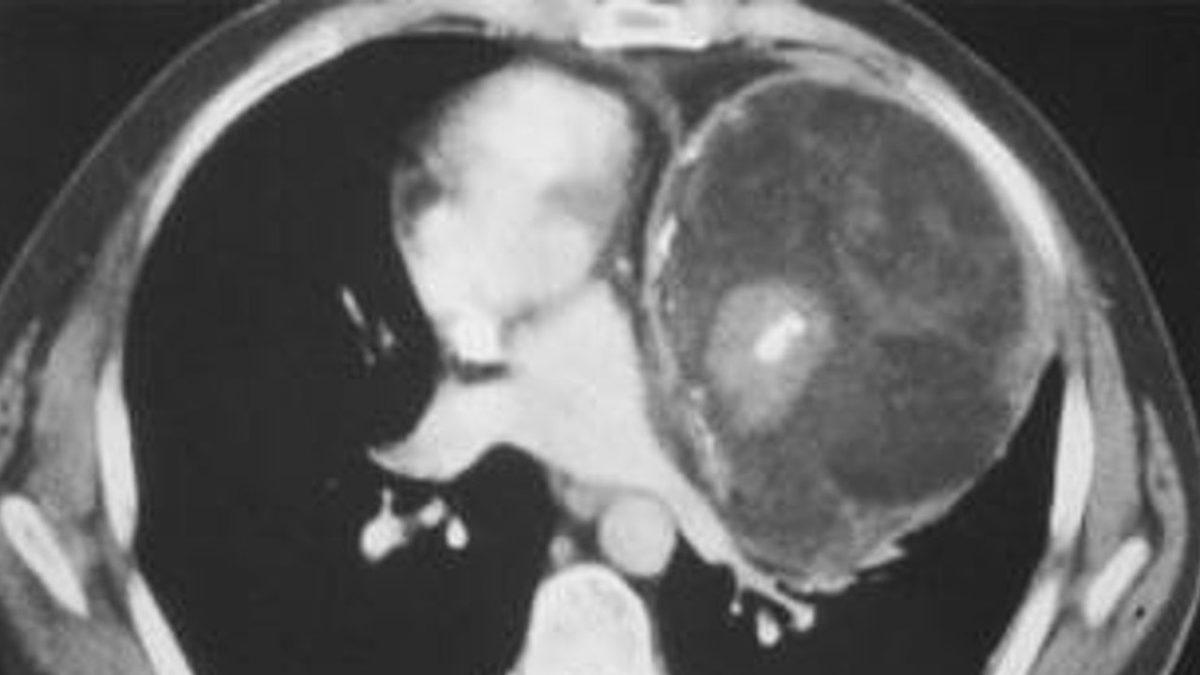

Bu sendromu gösteren fetüsün muayene esnasında karnı şiş, aynı zamanda yumuşaktı ve karnındaki kitleler belirgin bir şekilde ele geliyordu. Kitle fetüs görünümünde, uzuv benzeri yapılara, anormal iskelet ve bağırsak gelişime sahipti.

Olguların yaklaşık %80'inde bu anormal durum, normal fetüsün vücudunda karnın arka bölgesinde ortaya çıkıyor ancak göğüs, kasık ve kuyruk sokumu gibi vücudun diğer bölgelerinde de görülebiliyor.

Tanı ve tedavi için ise fetüs içinde yeni bir fetüs oluşumuna sebebiyet veren bu kitle, yeni doğan bebeklerin vücutlarına potansiyel olarak zarar verirken, ameliyatla çıkarılmalı ve incelenmelidir.

Fetüs içinde fetüse sebep olan kitlelerin de bir tümör türü olan “teratom”un da tanısı oldukça zordur ve fetüs oluşumuna sebep olan kitleler çoğunlukla teratom zannedilebilir.

Teratom genellikle yumurtalık, testis, karın zarı ve kuyruk sokumunda görülürken FIF, yetersiz kan akışı nedeniyle büyümeyi durdurabilen amniyotik kesede bulunur. Bunun yanında fetüs içinde fetüse sebebiyet veren kistler, iyi huylu ve göbek kordonunun yapısına benzer temiz bir kan kaynağına sahip.